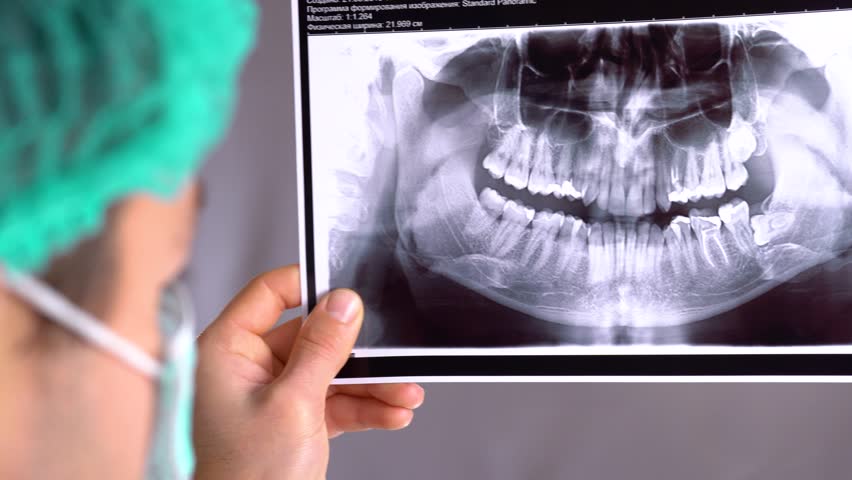

Digital Dental RVG Xray

Digital VATECH rvg xray helps to shoot xray of your dentition with almost zero exposure rate to radiations.Xray is digitally converted through software into image which can be seen within seconds onto computer screen. It helps in accurate diagnosis and treatment planning. Xray machine at Supreme Dental Hospital is ACTEON DC xray (France) and approved with AERB (Gvt. Of India)